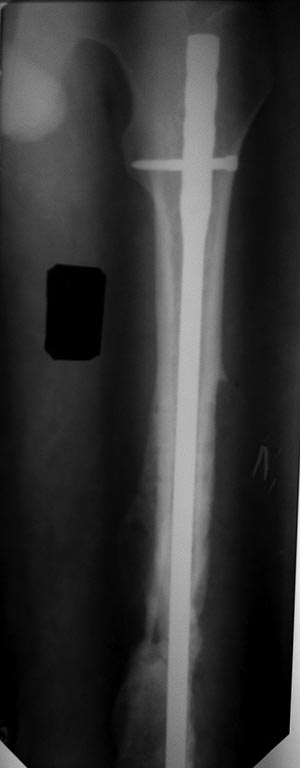

Ситуация немножко напоминает давным-давно тут обсуждавшийся случай - см. тут.

То есть и сейчас вполне уместно заштифтовать в два этапа - то есть сначала исправить аппаратом длину и ось, а пациент пока движения в колене постарается подразработать.

Вообще, можно заштифтовать и одномоментно - аппаратом можно разобщить и вправить отломки сразу, а при стойко неразгибающемся колене штифтовать через артротомию коленного сустава, может, заодно там чего мобилизовать.